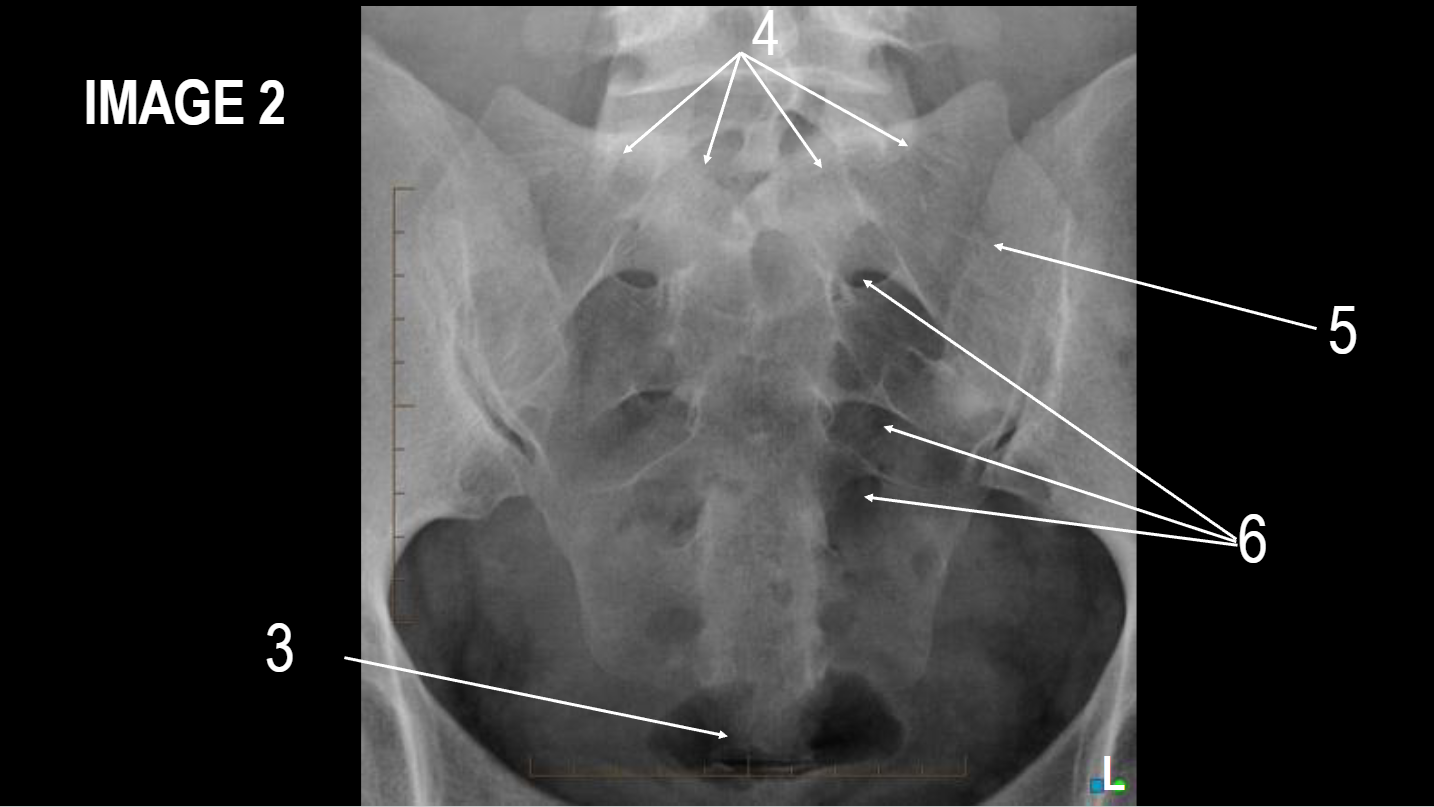

A

left iliac crest

B

ASIS

C

ischial body

D

ischial tuberosity

E

pubic symphysis

F

inferior ramus of pubis

G

superior ramus of pubis

H

ischial spine

I

acetabulum

J

femoral neck

K

greater trochanter

L

femoral head

M

ala/wing of ilum

What projection is this

AP Pelvis